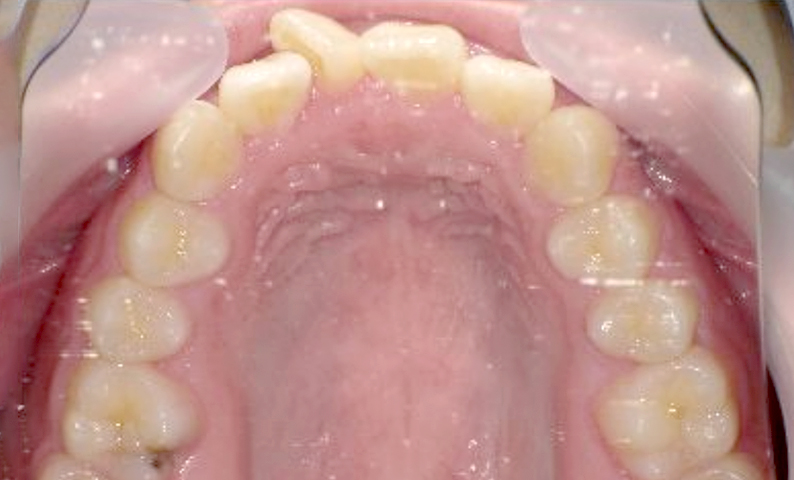

症例_002 上下顎の部分矯正

治療期間:7ヶ月金額:54万円+税女性前歯のガタガタ出っ歯八重歯